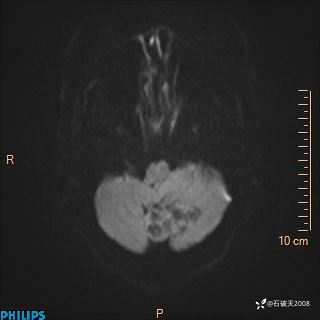

DWI